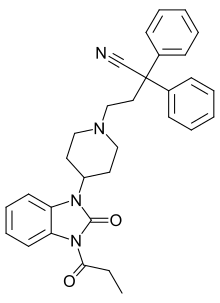

Benzimidazoles

Structures

| Benzimidazoles | ||||

|---|---|---|---|---|

|

|

|

|

|